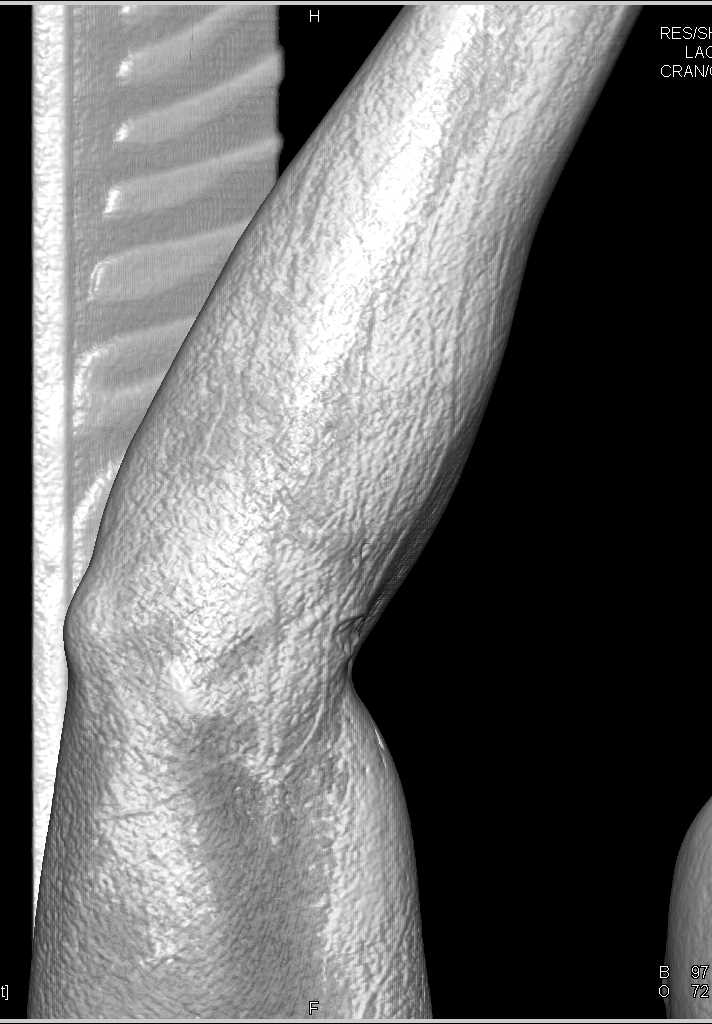

Soft Tissue Injury with Patent Vessels